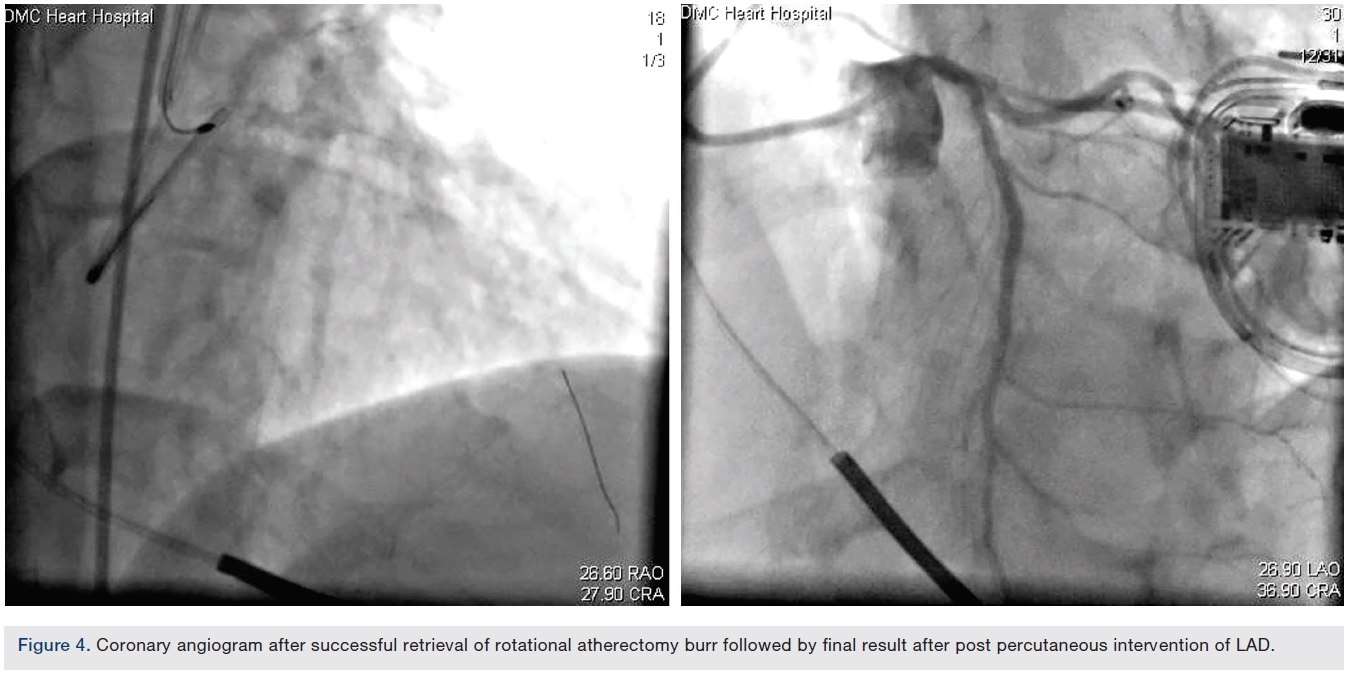

A 69-year-old male with coronary artery disease, prior left anterior descending artery (LAD) stenting, ischemic cardiomyopathy, hypertension, diabetes, and hyperlipidemia underwent coronary angiography for worsening angina and anterior ischemia on stress testing. Coronary vessels were heavily calcified. A prior stent was visualized in the proximal and mid LAD with 50% in-stent stenosis proximally and 95% sub-total occlusion just distal to the stent or within the stent (difficult to delineate due to severe calcification). The LAD lesion was thought to be the culprit. Rotational atherectomy was undertaken due to the calcification distal to the stent.

A 6 French Ultimate 2 guide (Merit Medical) through a right radial approach was used to engage the left main. A Balance Middleweight (BMW) wire (Abbott Vascular) was passed distal to the LAD, then exchanged for an Extra Support RotaWire (Boston Scientific) via a Micro 14 catheter (Roxwood Medical). A 1.5 mm RotaLink Plus (Boston Scientific) was used for atherectomy and 2 runs were performed with no deceleration as per staff. The Rota burr popped through the lesion, then stalled.